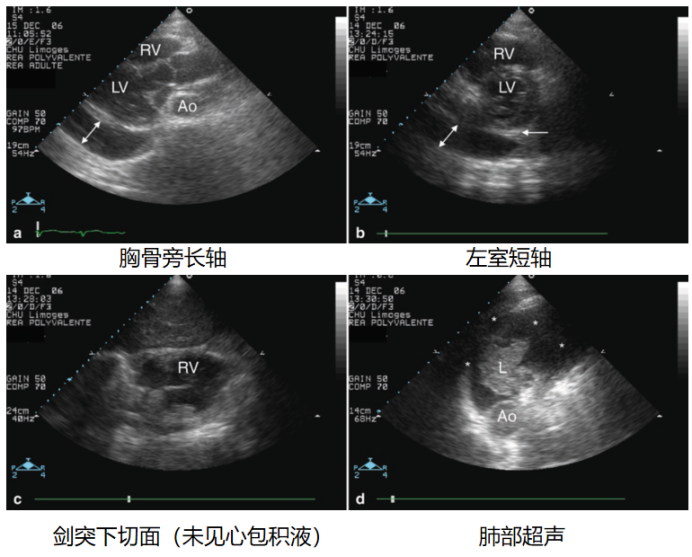

通过该患者多切面超声图像分析:①胸骨旁长轴切面(图9a):于后心包区域可见无回声区,需鉴别心包积液与胸腔积液。从解剖定位看,无回声区在主动脉(Ao)前方或外部。②左室短轴切面(图9b):无回声区显示更清晰,其位于左室后方,与心室壁贴合关系不紧密。③剑突下切面(图9c):未探及明显心包积液征象(心包腔内无特征性无回声区)。④肺部超声(图9d):胸腔内明确探及无回声区(*号标识的区域)。结合前序切面的定位分析,可印证胸骨旁长轴的无回声区为胸腔积液,而非心包积液。

图片

9  心包积液与胸腔积液的超声鉴别